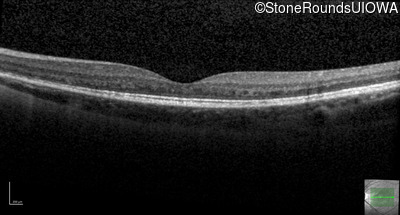

Optical Coherence Tomography - Left - 20/50

Exemplar / OCT Stack